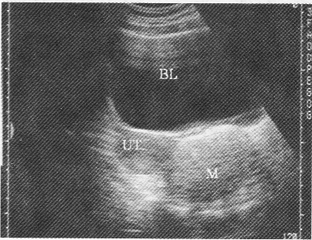

3.如圖,女性,25歲,無明顯自覺癥狀,盆腔橫斷面,最可能的診斷是

A.附件區炎性包塊

B.異位妊娠

C.畸胎瘤

D.黃體囊腫

E.正常聲像圖

正確答案:C解題思路:附件區見無回聲暗區,邊界清晰,其內見強回聲水平分界線,在線上方為脂質成分,呈均勻密集細小光點,水平線下方為無回聲暗區。